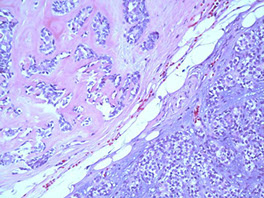

Adenoid Cystic Carcinoma

- aka cylindroma

~1/15 of all salivary gland tumors; seen in older women

- mostly (60%) seen in minor salivary glands, esp in the palate; (MC malignant tumor of minor salivary glands)

Have extensively invasive growth patterns, esp perineural invasion

Micro: Biphasic c ductal lining and ME cells with cribriform, tubular or solid pattern and hyaline material filling the spaces bwt tumors (stromal hyalinization [thick BM])

- usually contains at least some cribriform nests (Swiss cheese) filled c myxoid (blue goo), but may not be present on small bx

- tumor cells should not have intracytoplasmic mucin (found in MEC) - mucin is secreted into pseudocysts - also shound not have squamous metaplasia

- considered high-grade if >30% has solid growth pattern - has calcification / comedonecrosis in high grade

Cytology: carrot-shaped

Genes: LOH at 6q23-35, MYB-NFIB in 1/2

IHC: (+) ME pos for CK (lumen epithelial cells) / p63 (basal-myoepithelial cells) / calponin / SMA / S100 / GFAP, epithelium pos for CK/EMA/CEA/c-kit (luminal) and CD117???

DDx: PLGA (PLGA has less mits, less hyperchromasia, less dense fibrous stroma, smaller nests and less nuclear polymorphism); PA

Tx: Radical excision and rads

Px: Tend to recur and met; thus are high risk and have relatively low 5- and 10-year survivals (MC mets to lung)

- high tendency for perineural invasion

Adenoid cystic ca

High grade adenoid cystic ca c comedo necrosis